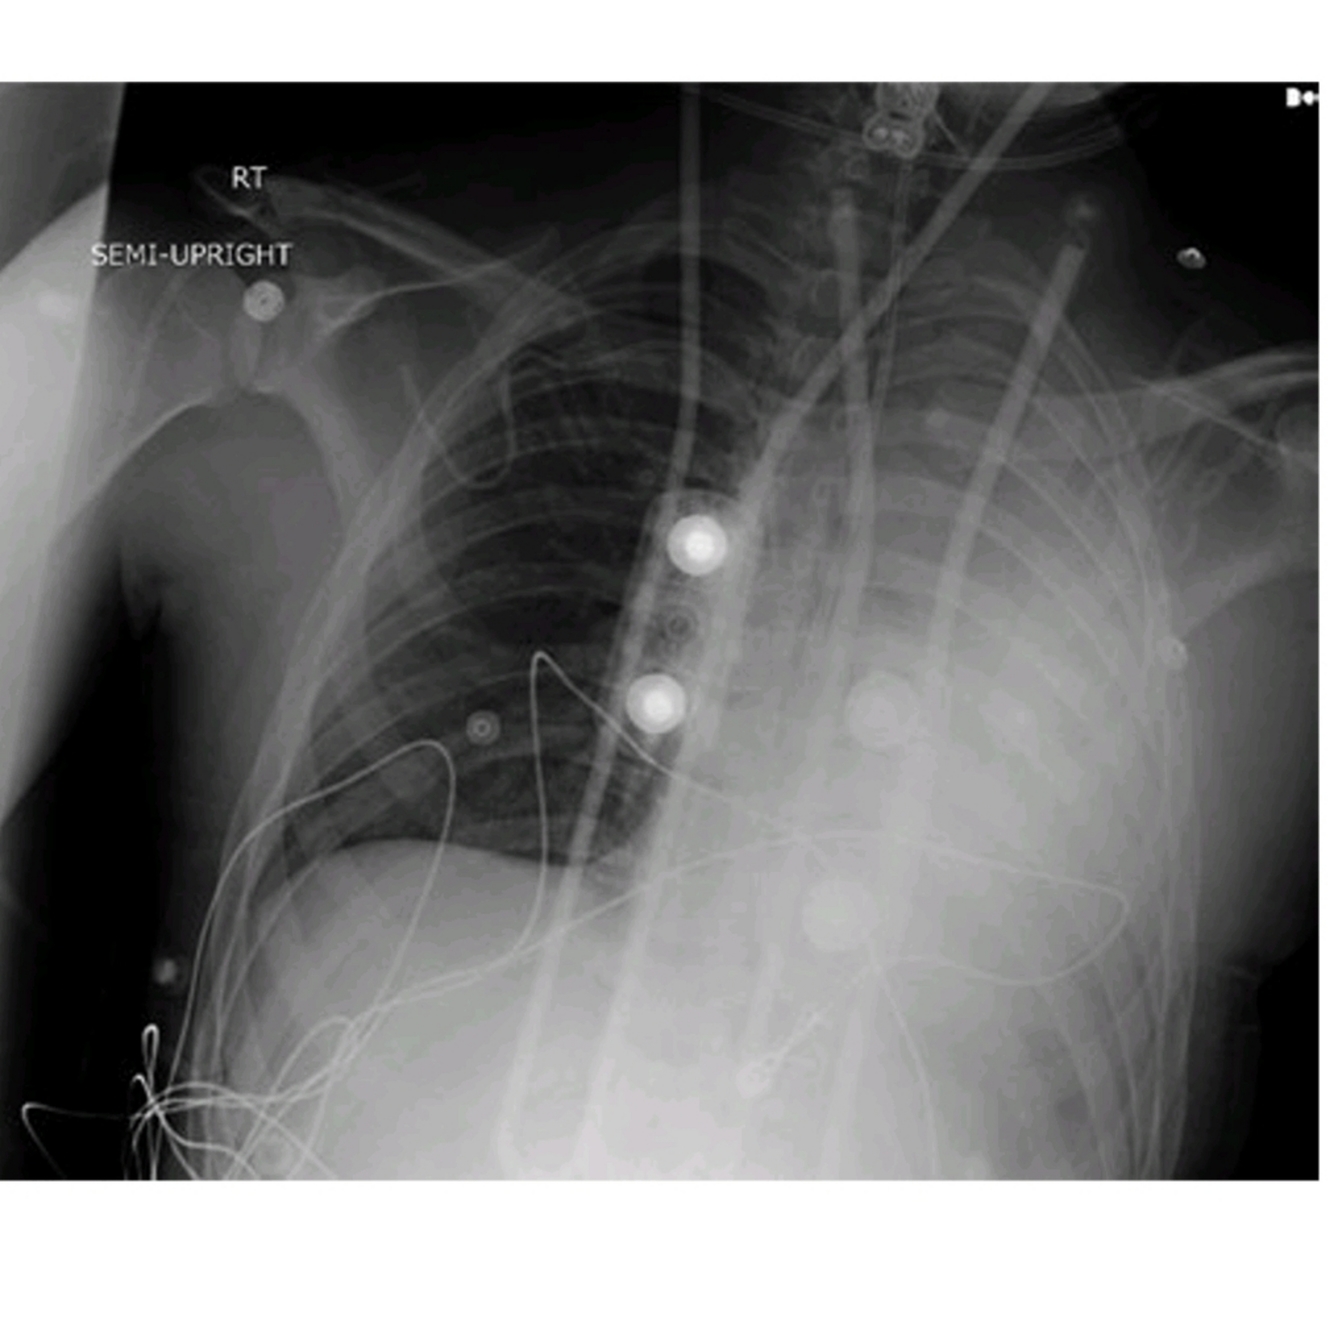

What do the images above show and what is the differential diagnosis based on the appearance seen in the images above?

○ The chest X-ray (Fig. 47.1) shows diffuse bilateral coalescent opacities, whereas the CT chest (Fig. 47.2) shows ground-glass opacification, reflecting an overall reduction in the air content of the affected lung. It is also possible to visualize bronchial dilatation within areas of ground-glass opacification.

Differential diagnosis include

(a) ARDS,

(b) congestive heart failure,

(c) pulmonary hemorrhage,

(d) pneumonia,(

e) transfusion-related acute lung injury, and

(f) non-cardiogenic pulmonary edema.